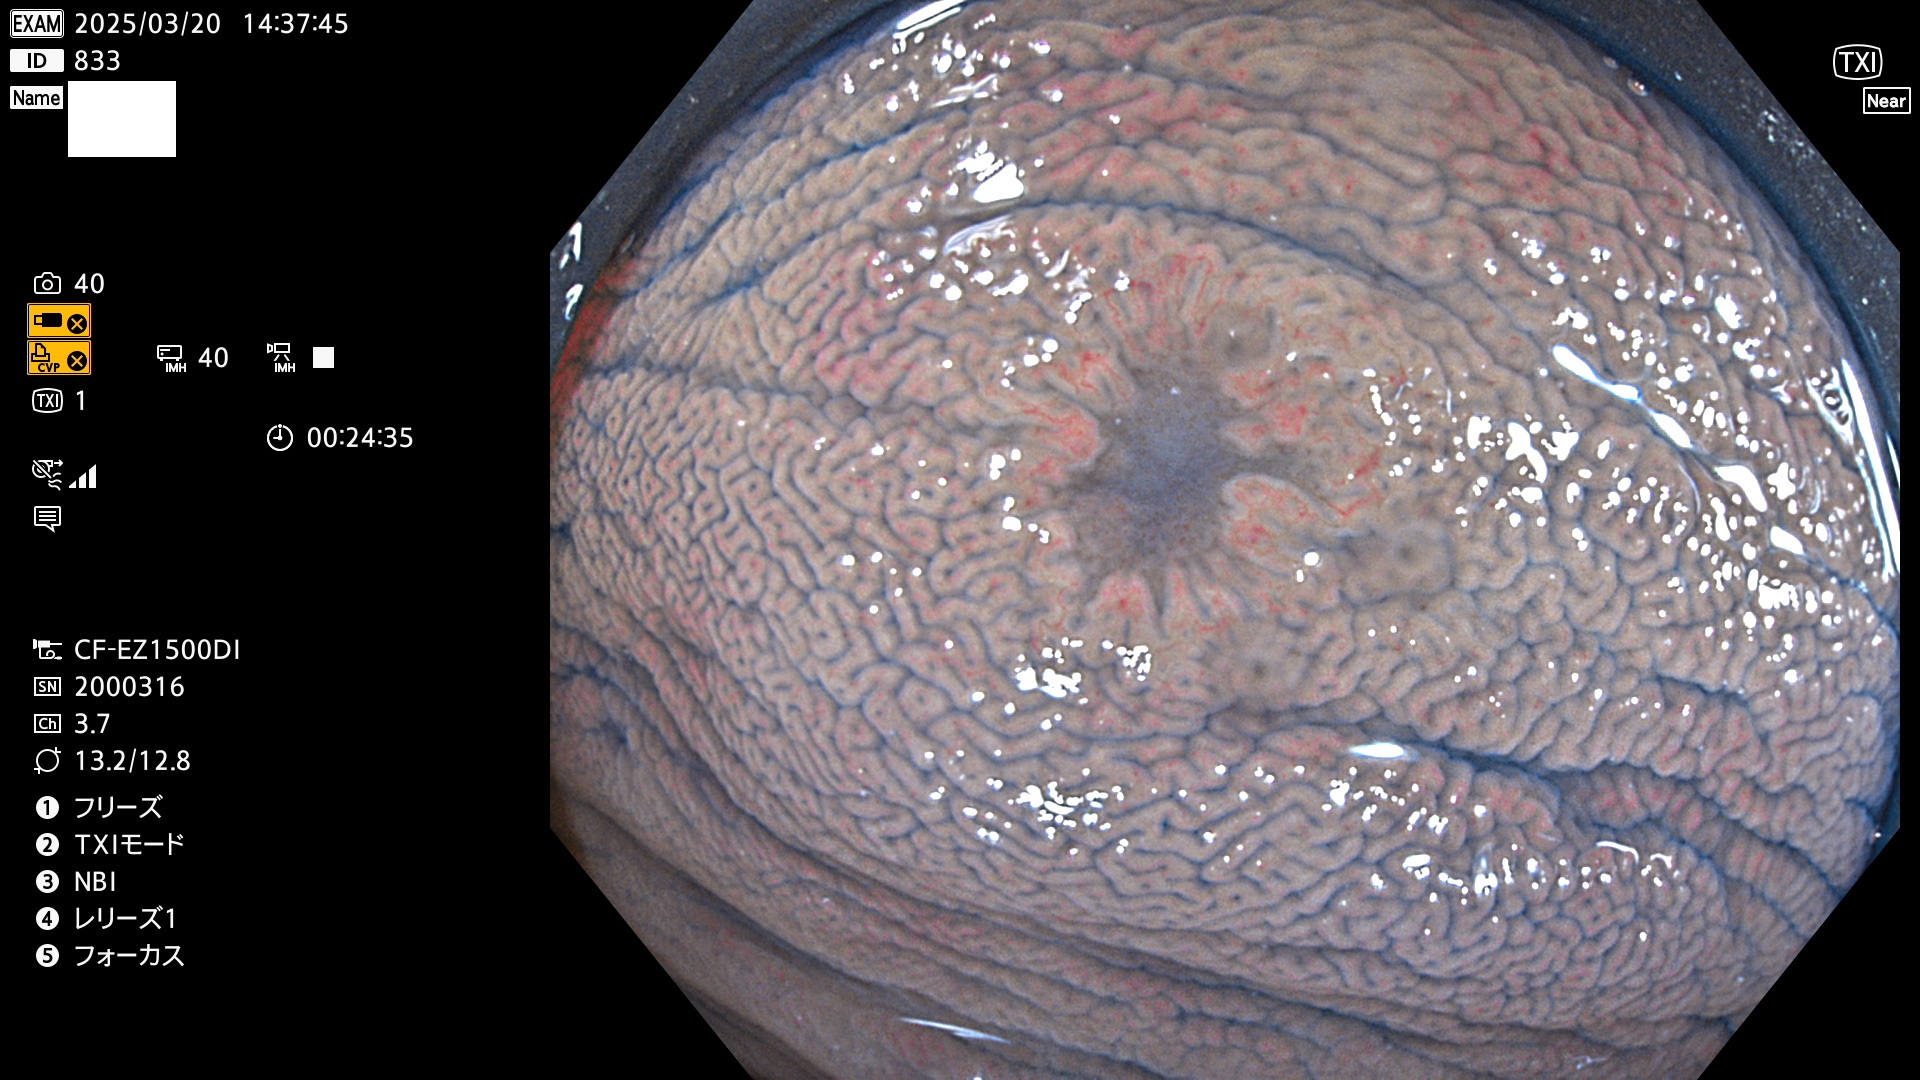

今週のUb、Uc型腺腫

完全に平坦な物をUb、陥凹している物をUcと呼びます。Ubは認識が困難で、Ucはびらん(炎症)と紛らわしいために見落とされやすく、「内視鏡後・大腸癌」の原因になります。

抽出の対象期間 2025年3月20日〜3月23日の4日間(48件の検査)10個 (10/48=21%)